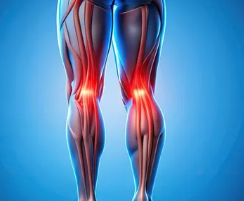

2. 오금 통증과 함께 나타나는 증상

✔ 무릎 뒤쪽 붓기 & 뻣뻣함 – 베이커 낭종, 관절염 가능성

✔ 통증이 걸을 때 심해짐 – 인대 손상 또는 좌골신경통 의심

✔ 무릎을 구부릴 때 찌릿한 느낌 – 반월상연골판 손상 가능성

✔ 다리가 저리고 감각이 둔해짐 – 신경 압박(허리 디스크, 좌골신경통) 가능성

✔ 무릎 뒤쪽에서 열감 & 붉은 기운 – 혈전 가능성(즉시 병원 방문 필요)

📌 즉, 오금 통증과 동반되는 증상을 통해 원인을 추측할 수 있으며, 혈관 문제라면 빠른 진료가 필요하다.